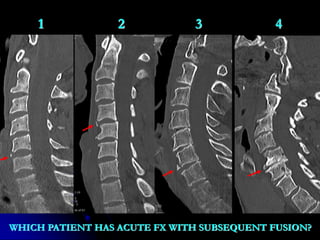

1 2 3 4

WHICH PATIENT HAS ACUTE FX WITH SUBSEQUENT FUSION?

3